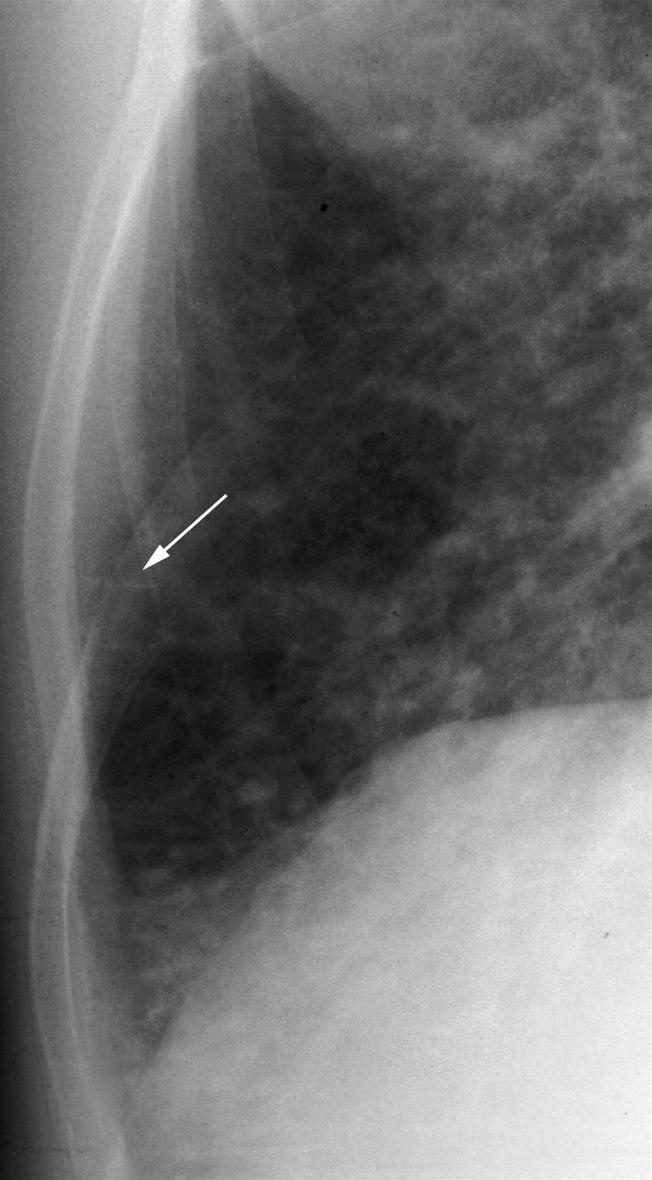

"Kerley B linjer" (pil) som er fortykkede interlobulærsepta på grunn av øket væskemengde.